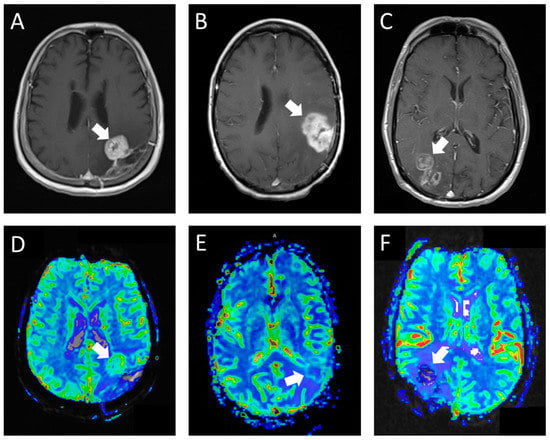

The second perfusion rating (the experimental group) was assigned in a blinded retrospective review by a fellowship-trained neuroradiologist, who also played a crucial role in developing the grading rubric for the experimental group. This neuroradiologist employed our novel perfusion scoring rubric (Table 1; Figure 1) to determine the perfusion scores. The structured criteria offered benchmarks for areas of high perfusion (normal cerebral cortex) and low perfusion (normal cerebral white matter). Studies predominantly resembling the cerebral cortex in tissue characteristics were classified as high perfusion, whereas those with perfusion levels between the cortex and white matter or with only limited tumor portions exhibiting rCBV similar to the cortex were deemed intermediate perfusion. Studies where the majority of the tumor resembled white matter were categorized as low perfusion. In cases where the studies were constrained by artifacts or technical failures, they were designated as not interpretable.

Figure 1. T1 post-contrast (A) and rCBV (D) in a patient with glioblastoma showing a nodule with marked enhancement and perfusion similar to areas of the normal cortex (hyperperfusion). The reresection demonstrated recurrent glioblastoma. T1 post-contrast (B) and rCBV (E) in a patient with glioblastoma showing a mass with marked solid enhancement and perfusion between the normal cortex and white matter (intermediate perfusion). The reresection demonstrated recurrent gliosarcoma with 60% tumor. T1 post-contrast (C) and rCBV (F) in a patient with glioblastoma showing heterogeneous areas of enhancement with perfusion similar to areas of normal white matter (hypoperfusion). The reresection demonstrated reactive brain tissue with organizing hematoma and the therapy effect.